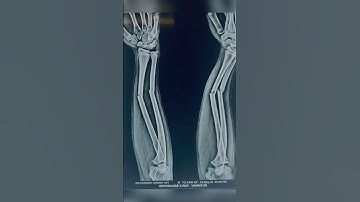

Correction of Maluniting fracture both bones forearm | Manipulation under short GA & casting | AHV